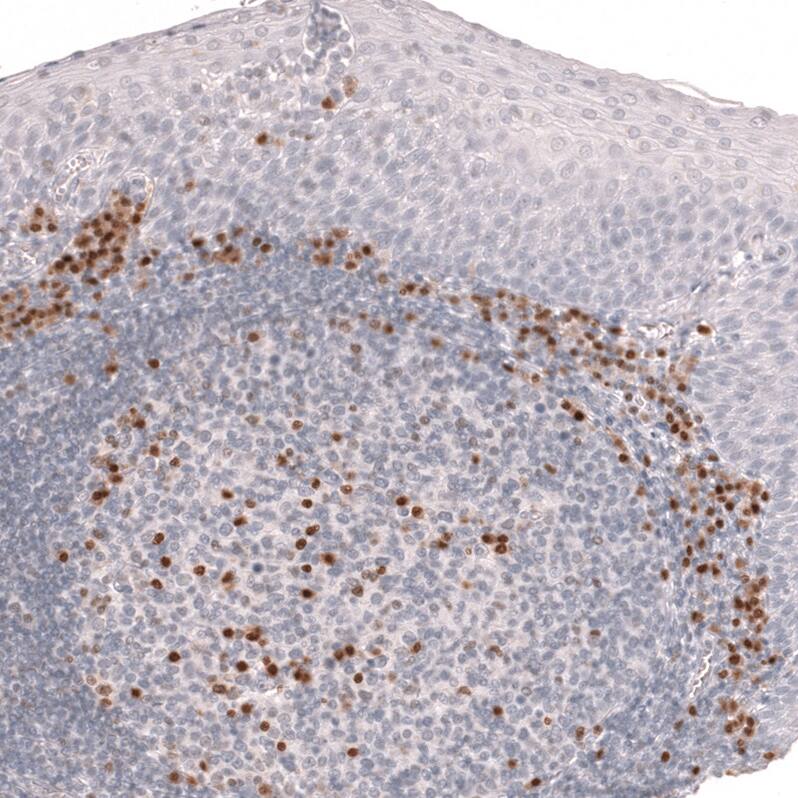

Immunohistochemistry-Paraffin: IRF4 Antibody (CL14615) [NBP3-26863]

Staining of human tonsil shows strong nuclear positivity in lymphoid cells.